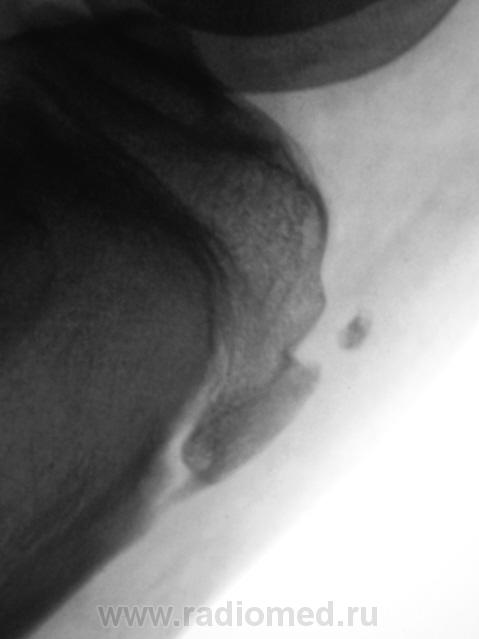

Кроме остеохондропатии бугристостей у пациента явная латеропозизия надколенников и бугристостей большеберцовых костей, что свидетельствует о дисплазии мыщелков бедренных костей, вероятнее всего клинически проявляющаяся болями в переднем отделе коленных суставов (под надколенниками).

Интересно было бы посмотреть на аксиальные снимки надколенников. Явно ожидается уплощение медиальных мыщелков и межмыщелковых углублений бедренных костей.

Буквально позавчера был сходный случай. Мальчик 15 лет.